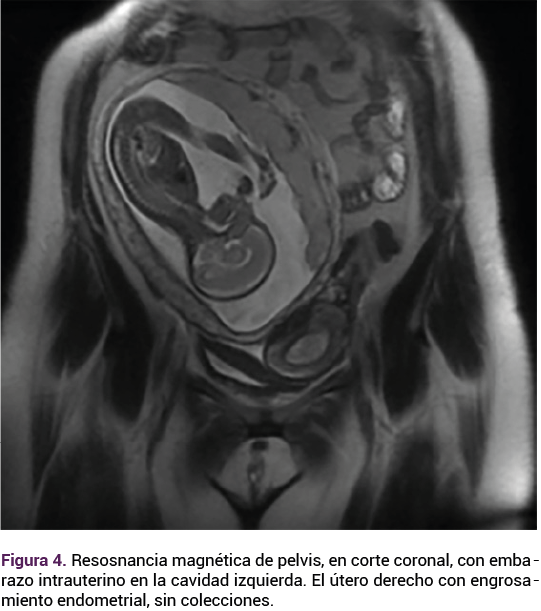

Sin concluir el protocolo de estudio (6 años después de su primer contacto) regresó con un embarazo espontáneo de 7.3 semanas de gestación para inicio de control prenatal. Durante la revisión del expediente electrónico se evidenciaron los antecedentes mencionados y la paciente informó el antecedente de infección de vías urinarias de repetición, así como la revisión por un urólogo quien le diagnosticó la ausencia del riñón izquierdo corroborado por medio de la TAC. Figura 2

Figura 2.

La paciente del caso reunió los criterios para síndrome de OHVIRA con útero didelfo, hemivagina obstruida y agenesia renal advertidos en la exploración física, en la tomografía axial computada y en la resonancia magnética durante el seguimiento ginecológico. Las más de las veces este síntoma se diagnostica en adolescentes que reúnen los datos mencionados; sin embargo, en la paciente del caso se diagnosticó en el embarazo. El caso es relevante por su asociación con un embarazo espontáneo, y por lo escasamente reportado en la bibliografía. Las pacientes con síndrome de OVHIRA tienen buen pronóstico reproductivo, como se evidencia en el caso, habiendo logrando dos embarazos espontáneos: el primero anembriónico y el segundo con finalización a término, sin complicaciones.